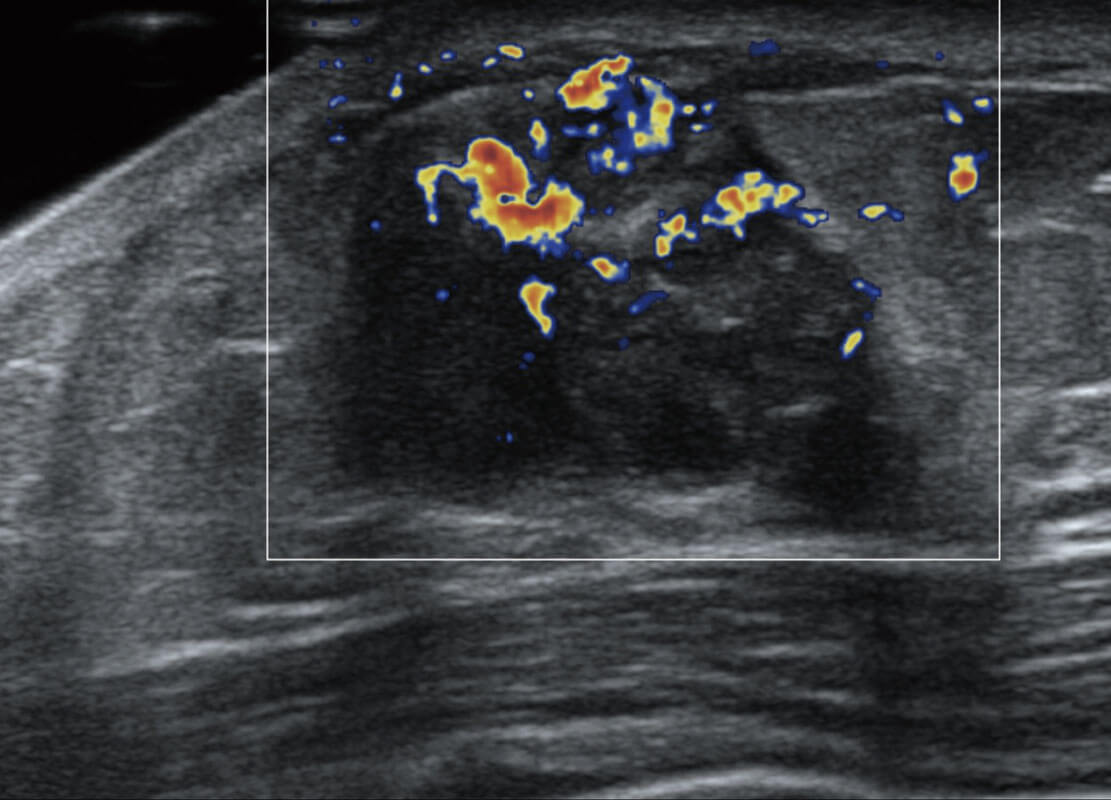

P60搭載寬頻帶線陣探頭、寬景成像、彈性成像技術(shù),為您提供乳腺應(yīng)用方案。P60支持高頻相控陣探頭、線陣探頭、腹部高頻探頭、腹部微凸探頭等,豐富的探頭群搭載敏感的彩色血流成像,適用于新生兒多種臟器檢測要求,滿足新生兒篩查需求。

乳腺導(dǎo)管癌

乳腺癌顯微血流